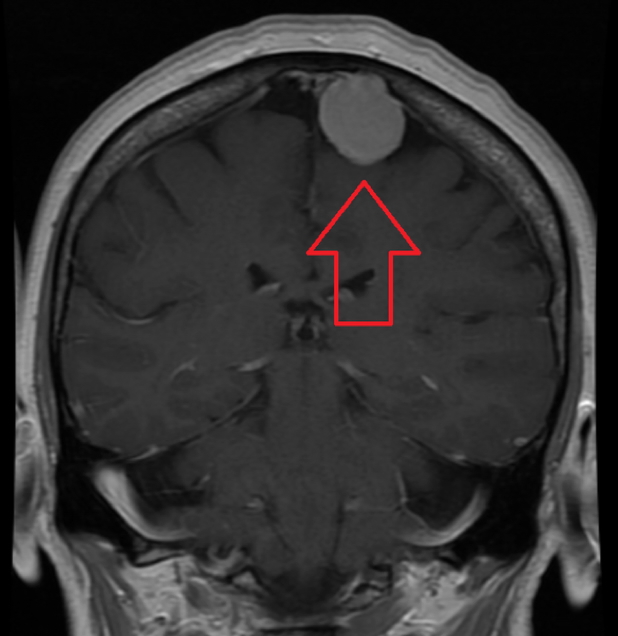

1. Meningioma

- Origin: Arachnoid cap cells

- Macro: Dura-attached, well-circumscribed, calcified

- Features:

- Benign and slow-growing

- Compression of adjacent brain tissue

- Headache, often worse during pregnancy

- Treatment: Surgical resection

- Prognosis: Excellent